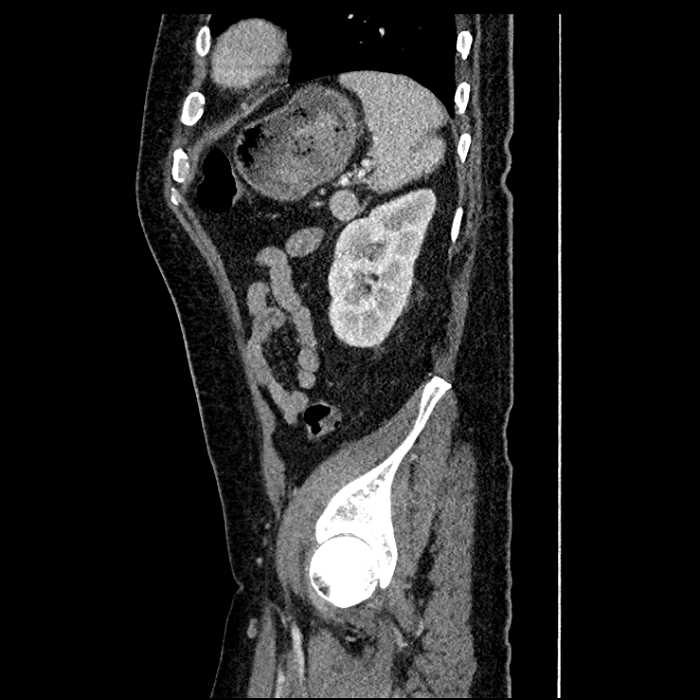

Age: 63

Sex: Male

Indication: Abdominal pain

• Large fluid density structure in hepatic segments 7 and 8 measuring 10 x 7 x 7 cm with internal septation and circumferential ill-defined low density compatible with edema

• Peripherally enhancing subcapsular collections along the anterior margin of the left hepatic lobe measuring 3 x 1 cm and 2 x 1 cm

• Clearly marginated fluid density structure in segment 7 and several other scattered tiny hypodensities, which likely represent cysts

• High grade stenosis of the left common iliac artery, with the left internal and external iliac arteries remaining patent

Acute sigmoid diverticulitis complicated by a small contained perforation and a large abscess in the right hepatic lobe. Additional small subcapsular abscesses along the anterior margin of the left hepatic lobe.

Additionally, loss of the normal fat plane between the peridiverticular collection and adjacent thickened loops of small bowel raises the potential for an enterocolonic fistula.

High grade stenosis of the left common iliac artery. The left external and internal iliac arteries are patent.

• The classic CT imaging appearance is a double target sign with internal low density surrounded by an internal enhancing rim (capsule) and a low density external rim (edema)

Hepatic abscess showing the double target sign with low density internally surrounded by a thin inner enhancing rim (red arrow) and ill-defined outer low density rim (yellow arrow). Blue arrow indicates an internal septation. Red arrows: additional smaller subcapsular abscesses. Red arrow: focal contained perforation associated with diverticulitis.